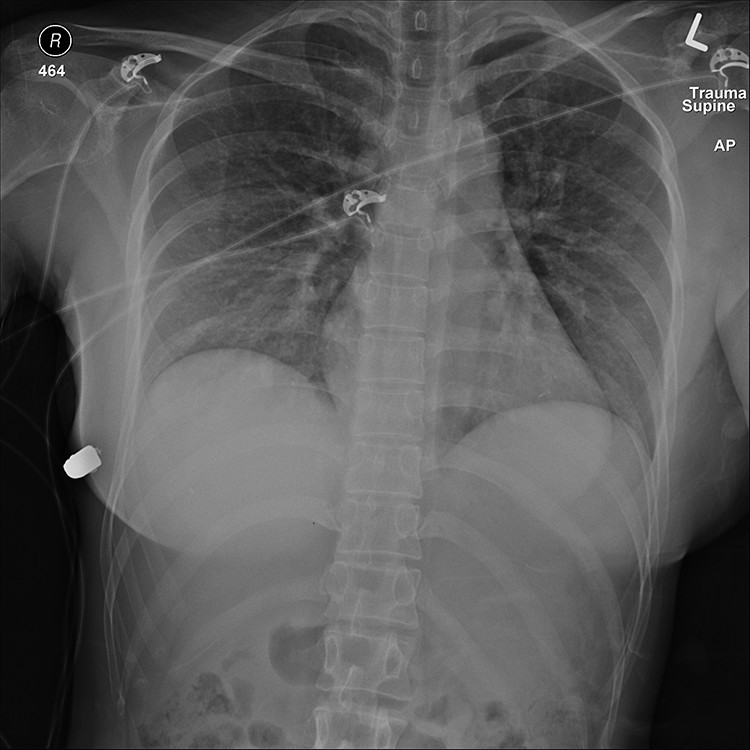

En Canadá recientemente se dio a conocer un extraño caso que sucedió hace dos años. Resulta que doctores de ese país contaron que una mujer recibió un disparo en su zona torácica y se salvó gracias a que sus implantes de silicona detuvieron la bala, la cual perforó parte del tejido pulmonar, pero no el corazón.

Luego de eso fue trasladada hasta un hospital de la ciudad antes mencionada, donde se descubrió que tenía una bala incrustada en la parte superior de su seno izquierdo, la cual perforó parte de su pulmón y una costilla. Luego de analizar la herida, se determinó que le habían disparado a corta distancia.

Luego de las reconstrucciones del caso, los médicos establecieron que la bala había pasado por los dos implantes mamarios y únicamente generó daño en el tejido del pulmón.

En ese instante, y tras reconstruir la trayectoria del proyectil, el equipo determinó que la bala habría impactado en el corazón de la mujer de no haber sido por el implante del seno izquierdo

“Este implante cubre el corazón y la cavidad intratorácica y por lo tanto probablemente salvó la vida de la mujer”, indicaron desde el equipo de investigación, dirigido por el cirujano plástico Giancarlo McEvenue.